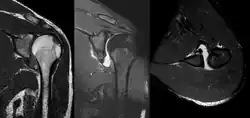

MRI of shoulder after dislocation with Hill-Sachs lesion and labral Bankart's lesion.

In young adults engaged in highly demanding activities shoulder surgery may be considered.[25] Arthroscopic surgery techniques may be used to repair the glenoidal labrum, capsular ligaments, biceps long head anchor or SLAP lesion or to tighten the shoulder capsule.[26]